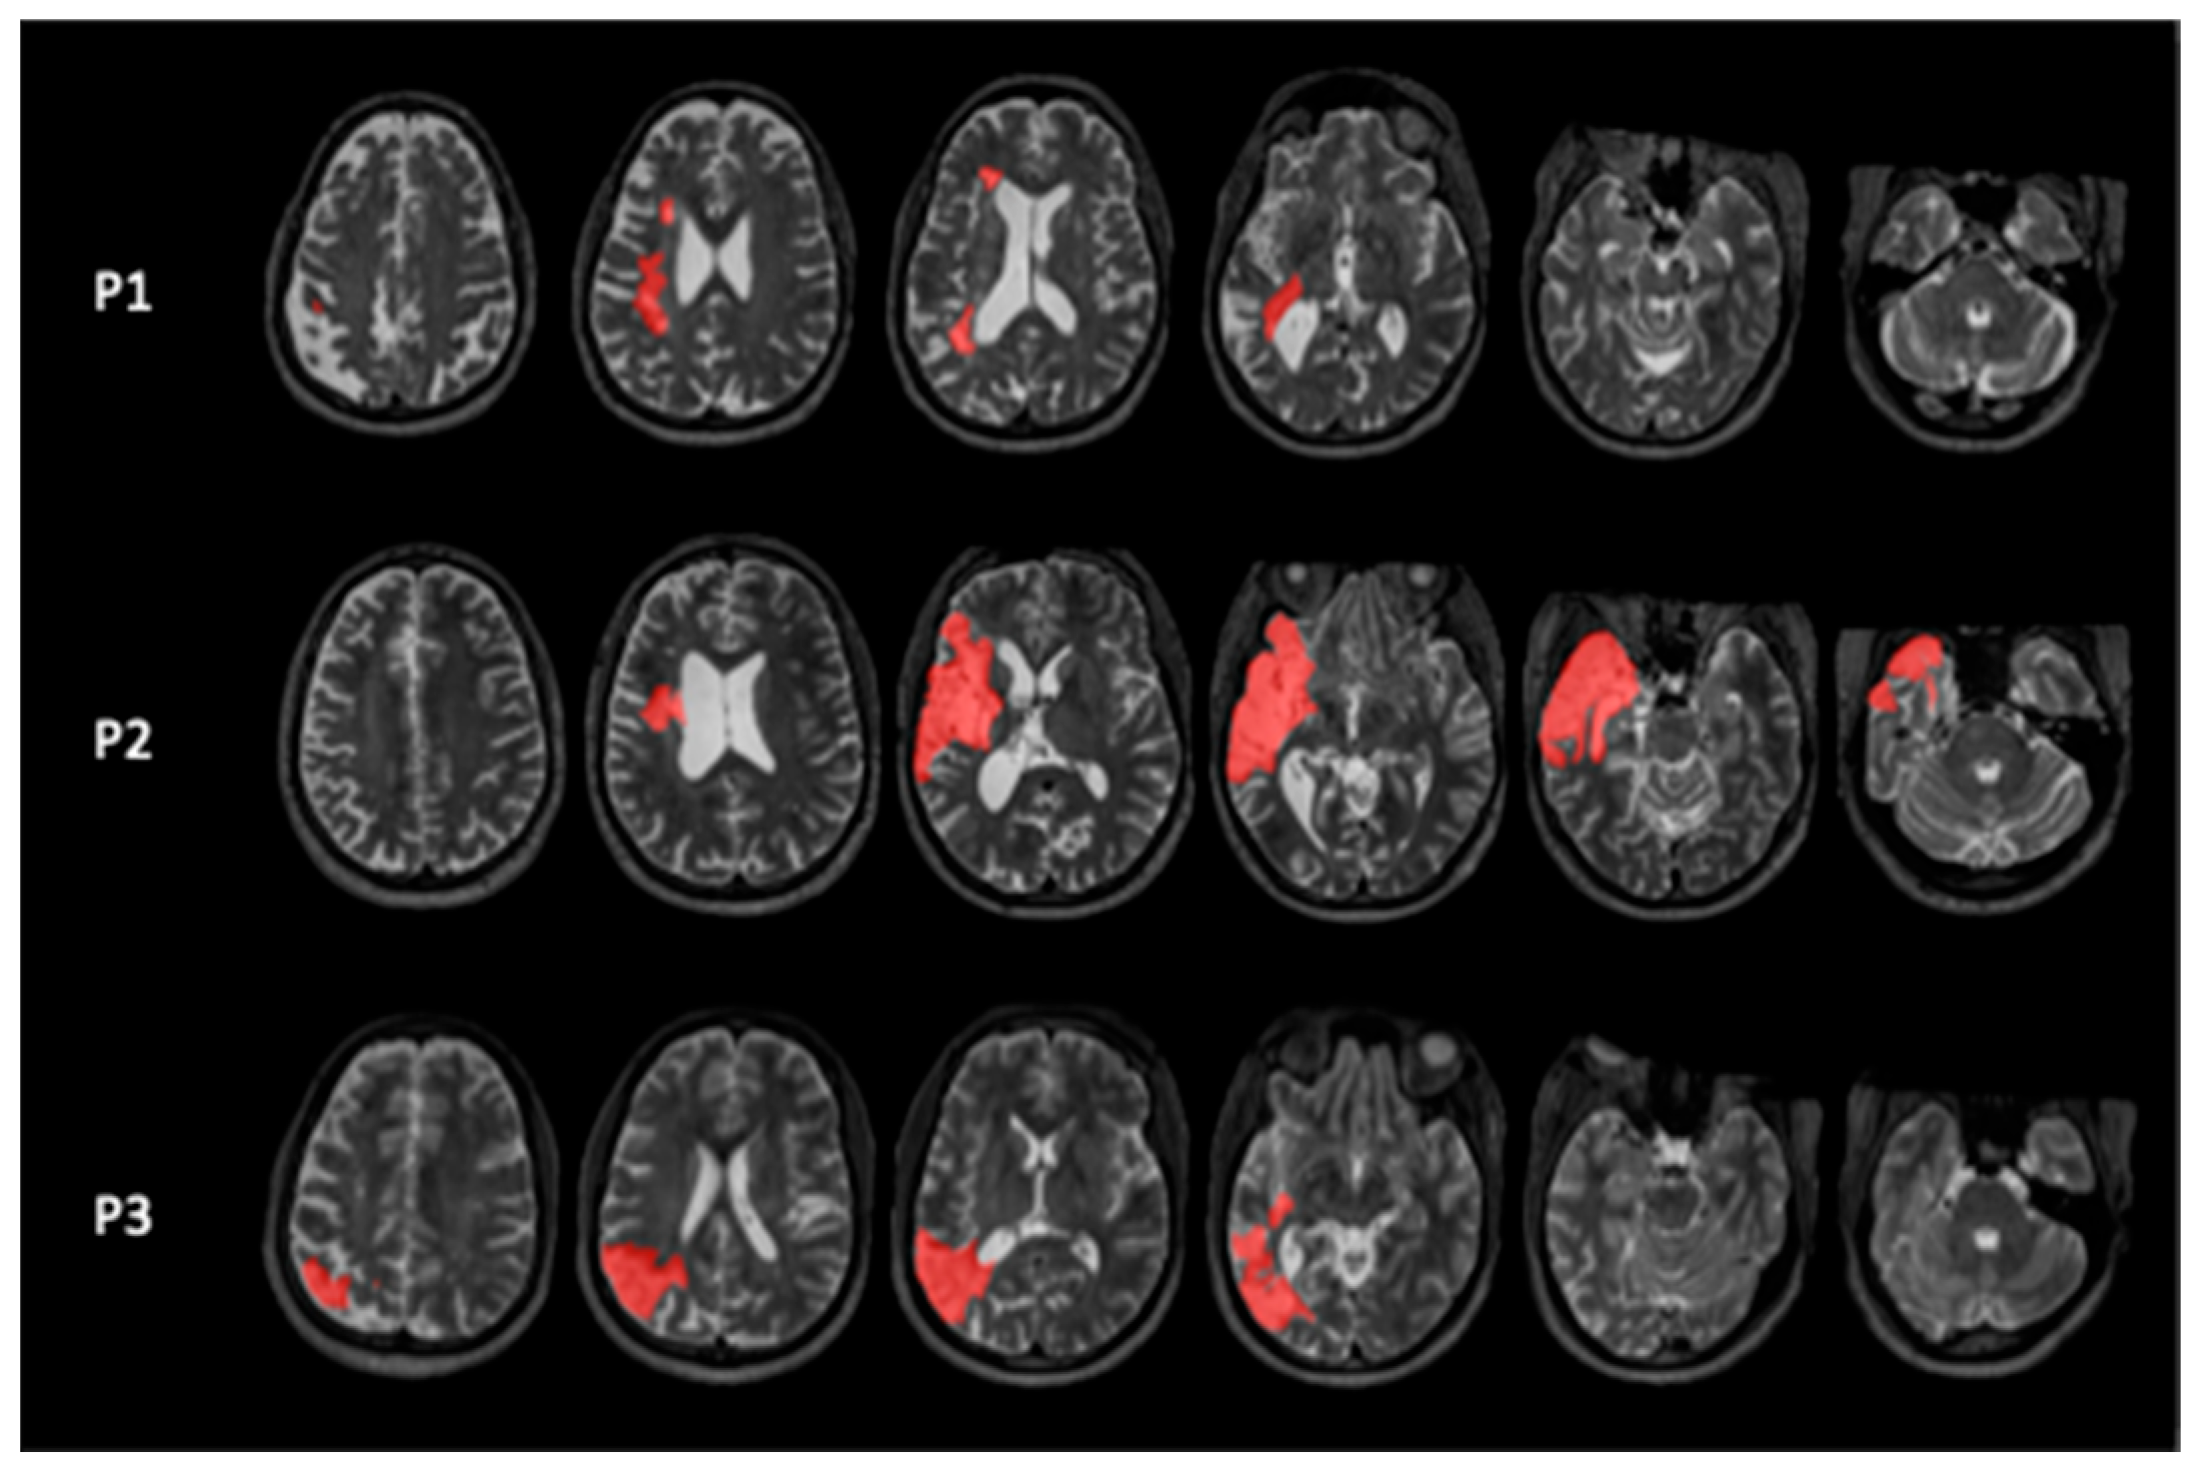

2.1. Participants